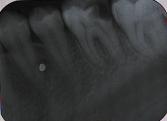

[感染根菅治療] 歯髄が腐敗して根の先端周囲に炎症が波及した場合の治療です。

術前

術中

術後